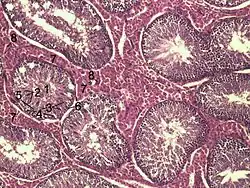

Při běžném stavu slouží myofibroblasty spíše jako podpůrné buňky. Umí se stahovat díky dynamickému cytoskeletu a zároveň produkují kolagen, významnou složku extracelulárního matrix. Hlavní roli však přebírají v době po zranění, kdy se zmnoží a účastní se stahování rány a tvorby jizvy. [1] Mezi sebou jsou navzájem propojeny buněčným spojem, kterému se říká nexus, neboli gap junction. [2] Při určení myofibroblastů se sleduje produkce“ alpha smooth muscle actin” (α-SMA), slouží tedy jako marker.

Při bližším zkoumání původu myofibroblastů je zřejmé, že se jedná o velmi komplexní problematiku. Je několik regulačních drah, transkripčních i epigenetických faktorů, které mají vliv na činnost a funkčnost myofibroblastů. Po mechanickém stresu tkáně fibroblasty začnou tvořit stresová vlákna, která jsou složena z cytoplasmatického aktinu a přeměňují se tím na proto-myofibroblasty. [3] Pro diferenciaci na myofibroblasty je potřeba zejména přítomnost transformačního faktoru TGF-β (Transforming growth factor beta). Dále pak také přítomnost speciálních extracelulárních proteinů jako např. varianty fibronektinu. [3]

Hlavní funkcí myofibroblastů je produkce kolagenu typu I a určitých cytokinů. Z toho je zřejmé, že hrají klíčovou roli při formování extracelulárního matrix, při léčení zánětů, jizvení a usazování pojivové tkáně. [2] Pomocí silných aktinových vláken stahují k sobě poškozené tkáně a vyplňují volný prostor při procesu, kterému se říká fibróza. Regulace tohoto projevu je však esenciální, a při nedostatečné kontrole mohou vznikat trvalé jizvy.